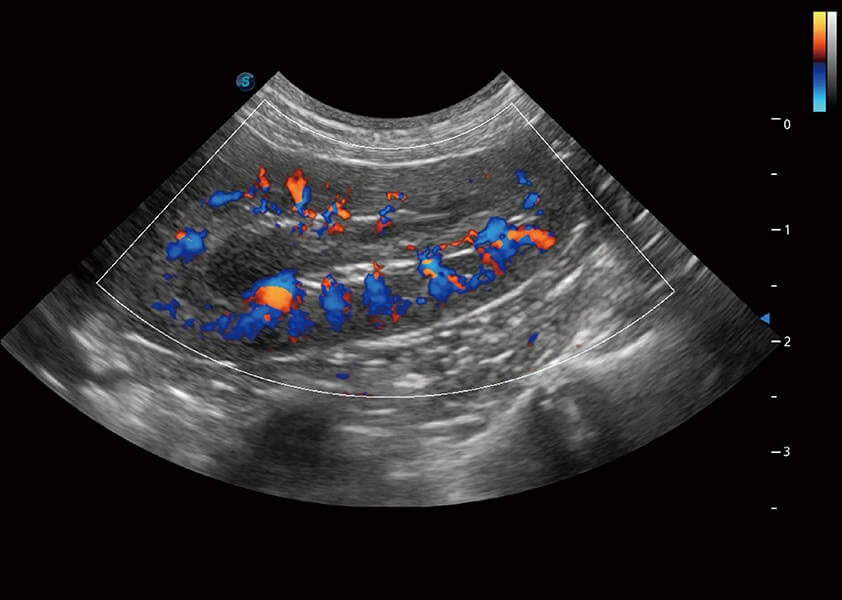

ProPet 60 作為一款高端臺式動物超聲設(shè)備,為動物醫(yī)生的日常診斷提供了一系列貼合動物臨床需求、解決臨床實際問題的高級成像功能。憑借全系列高清探頭,滿足醫(yī)生對腹部、心臟、生殖、淺表、肌骨等成像的所有需求,切實幫助您提升檢查效率,提高診斷信心。